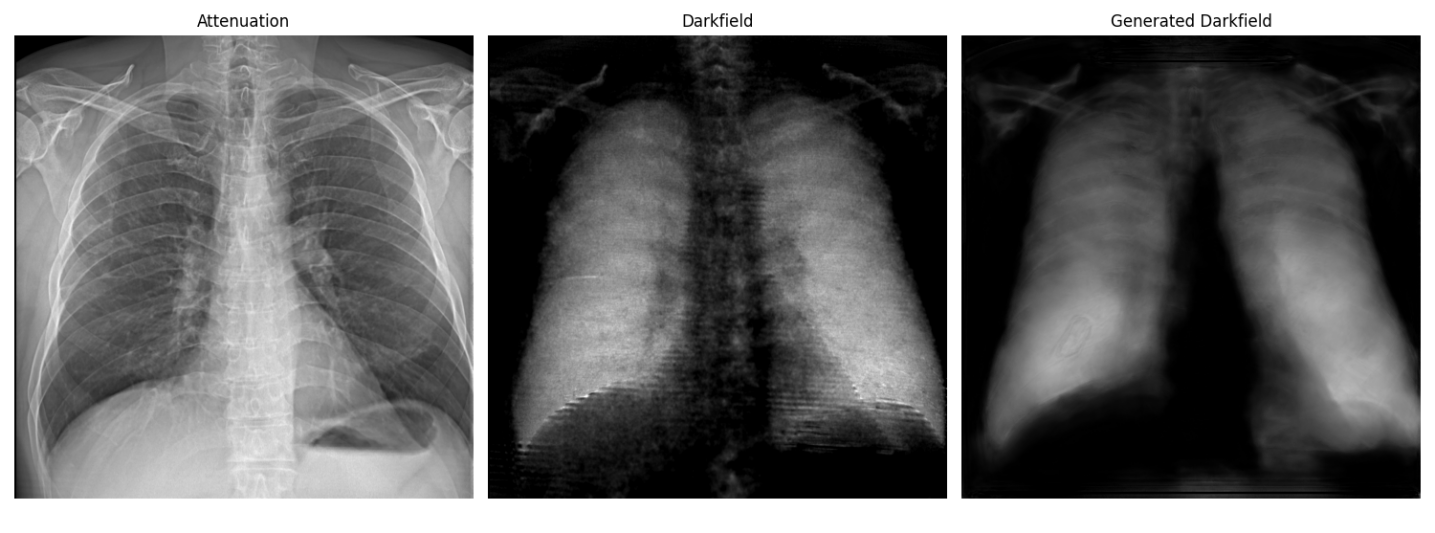

Attenuation Real dark-field Generated dark-field

Patient 1

Patient 2

Figure 3 shows the attenuation image, real dark-field and generated dark-field image for two patients. We find a good visual agreement between the generated dark-field and real measured dark-field. We particularly note pronounced differences in dark-field intensity across regions and patients. The model preserves these contrasts, which is critical for visualizing microstructural variation. We attribute the sharper appearance of the original dark-field images to additional scattering contributions that become visible through the dark-field signal reconstruction process. In particular, the horizontal stripe artifacts originating from the image formation process are not well captured by our model. Despite the remaining limitations, the model achieves a strong overall correspondence with real dark-field images.

The agreement between the real and generated dark-field is confirmed by the quantitative vales presented in table 1.

For all three metrics(MSE, PSNR, SSIM), we observe a consistent improvement across the model stages, indicating that the progressive refinement leads to higher image fidelity and better structural consistency. The final stage achieves the lowest MSE and highest SSIM and PSNR values, confirming that the model successfully reconstructs fine structural details.